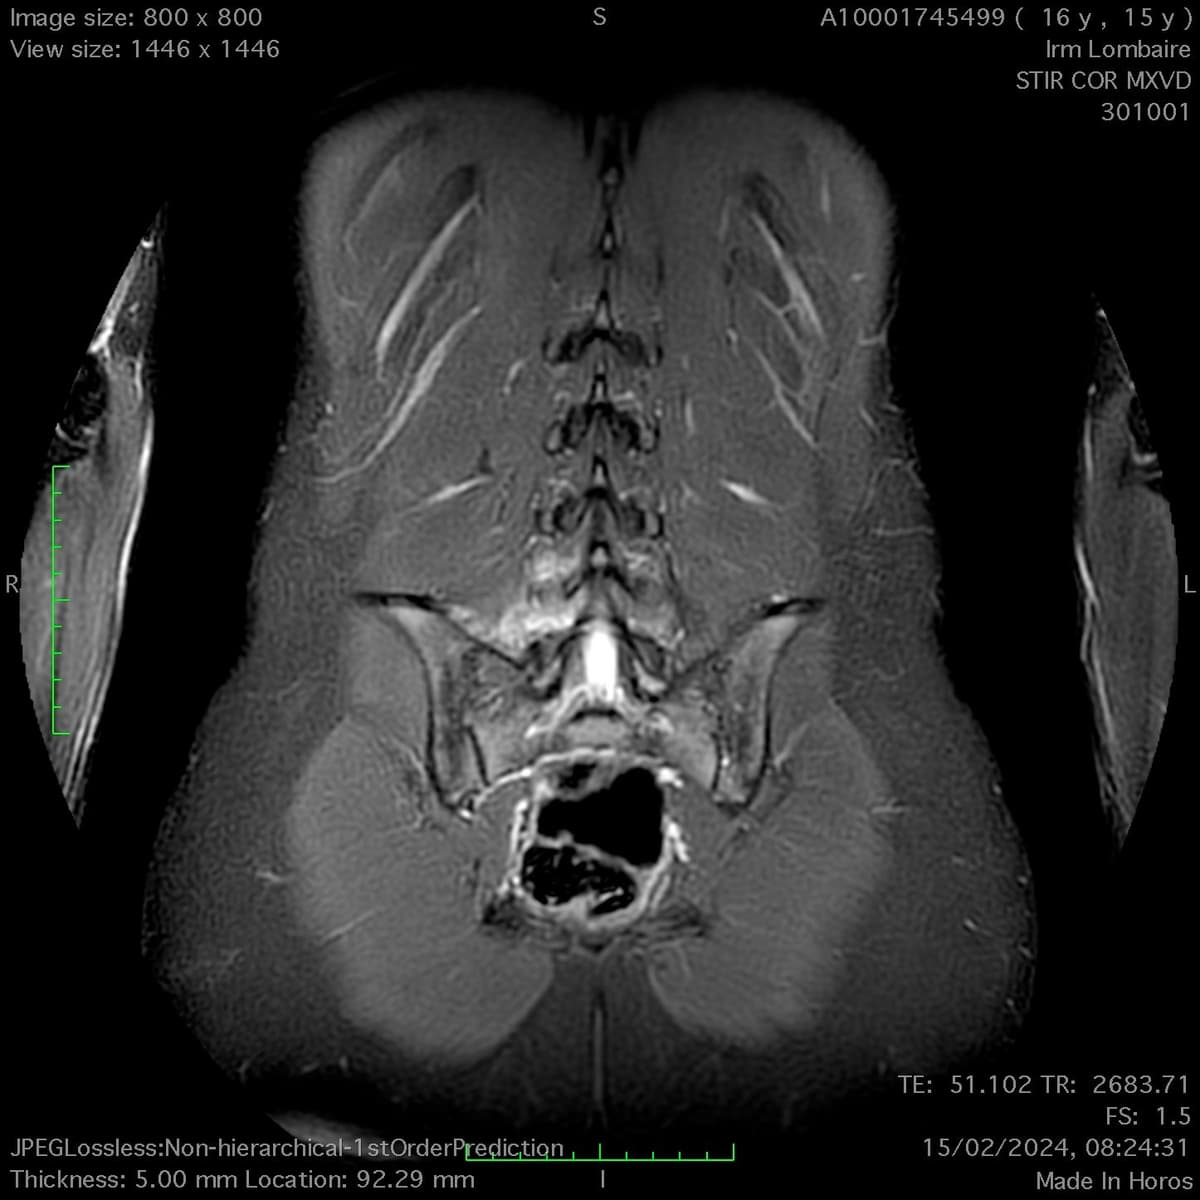

Lyse isthmique du rachis lombaire chez une adolescente pratiquant la natation

MRI